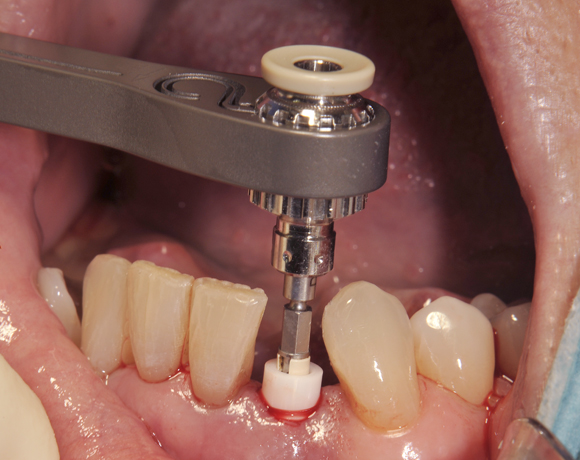

Am Beispiel dieses Patientenfalls wird gezeigt wie ein Einzelimplantat für den Unterkieferfrontzahn 33 eingesetzt wird.